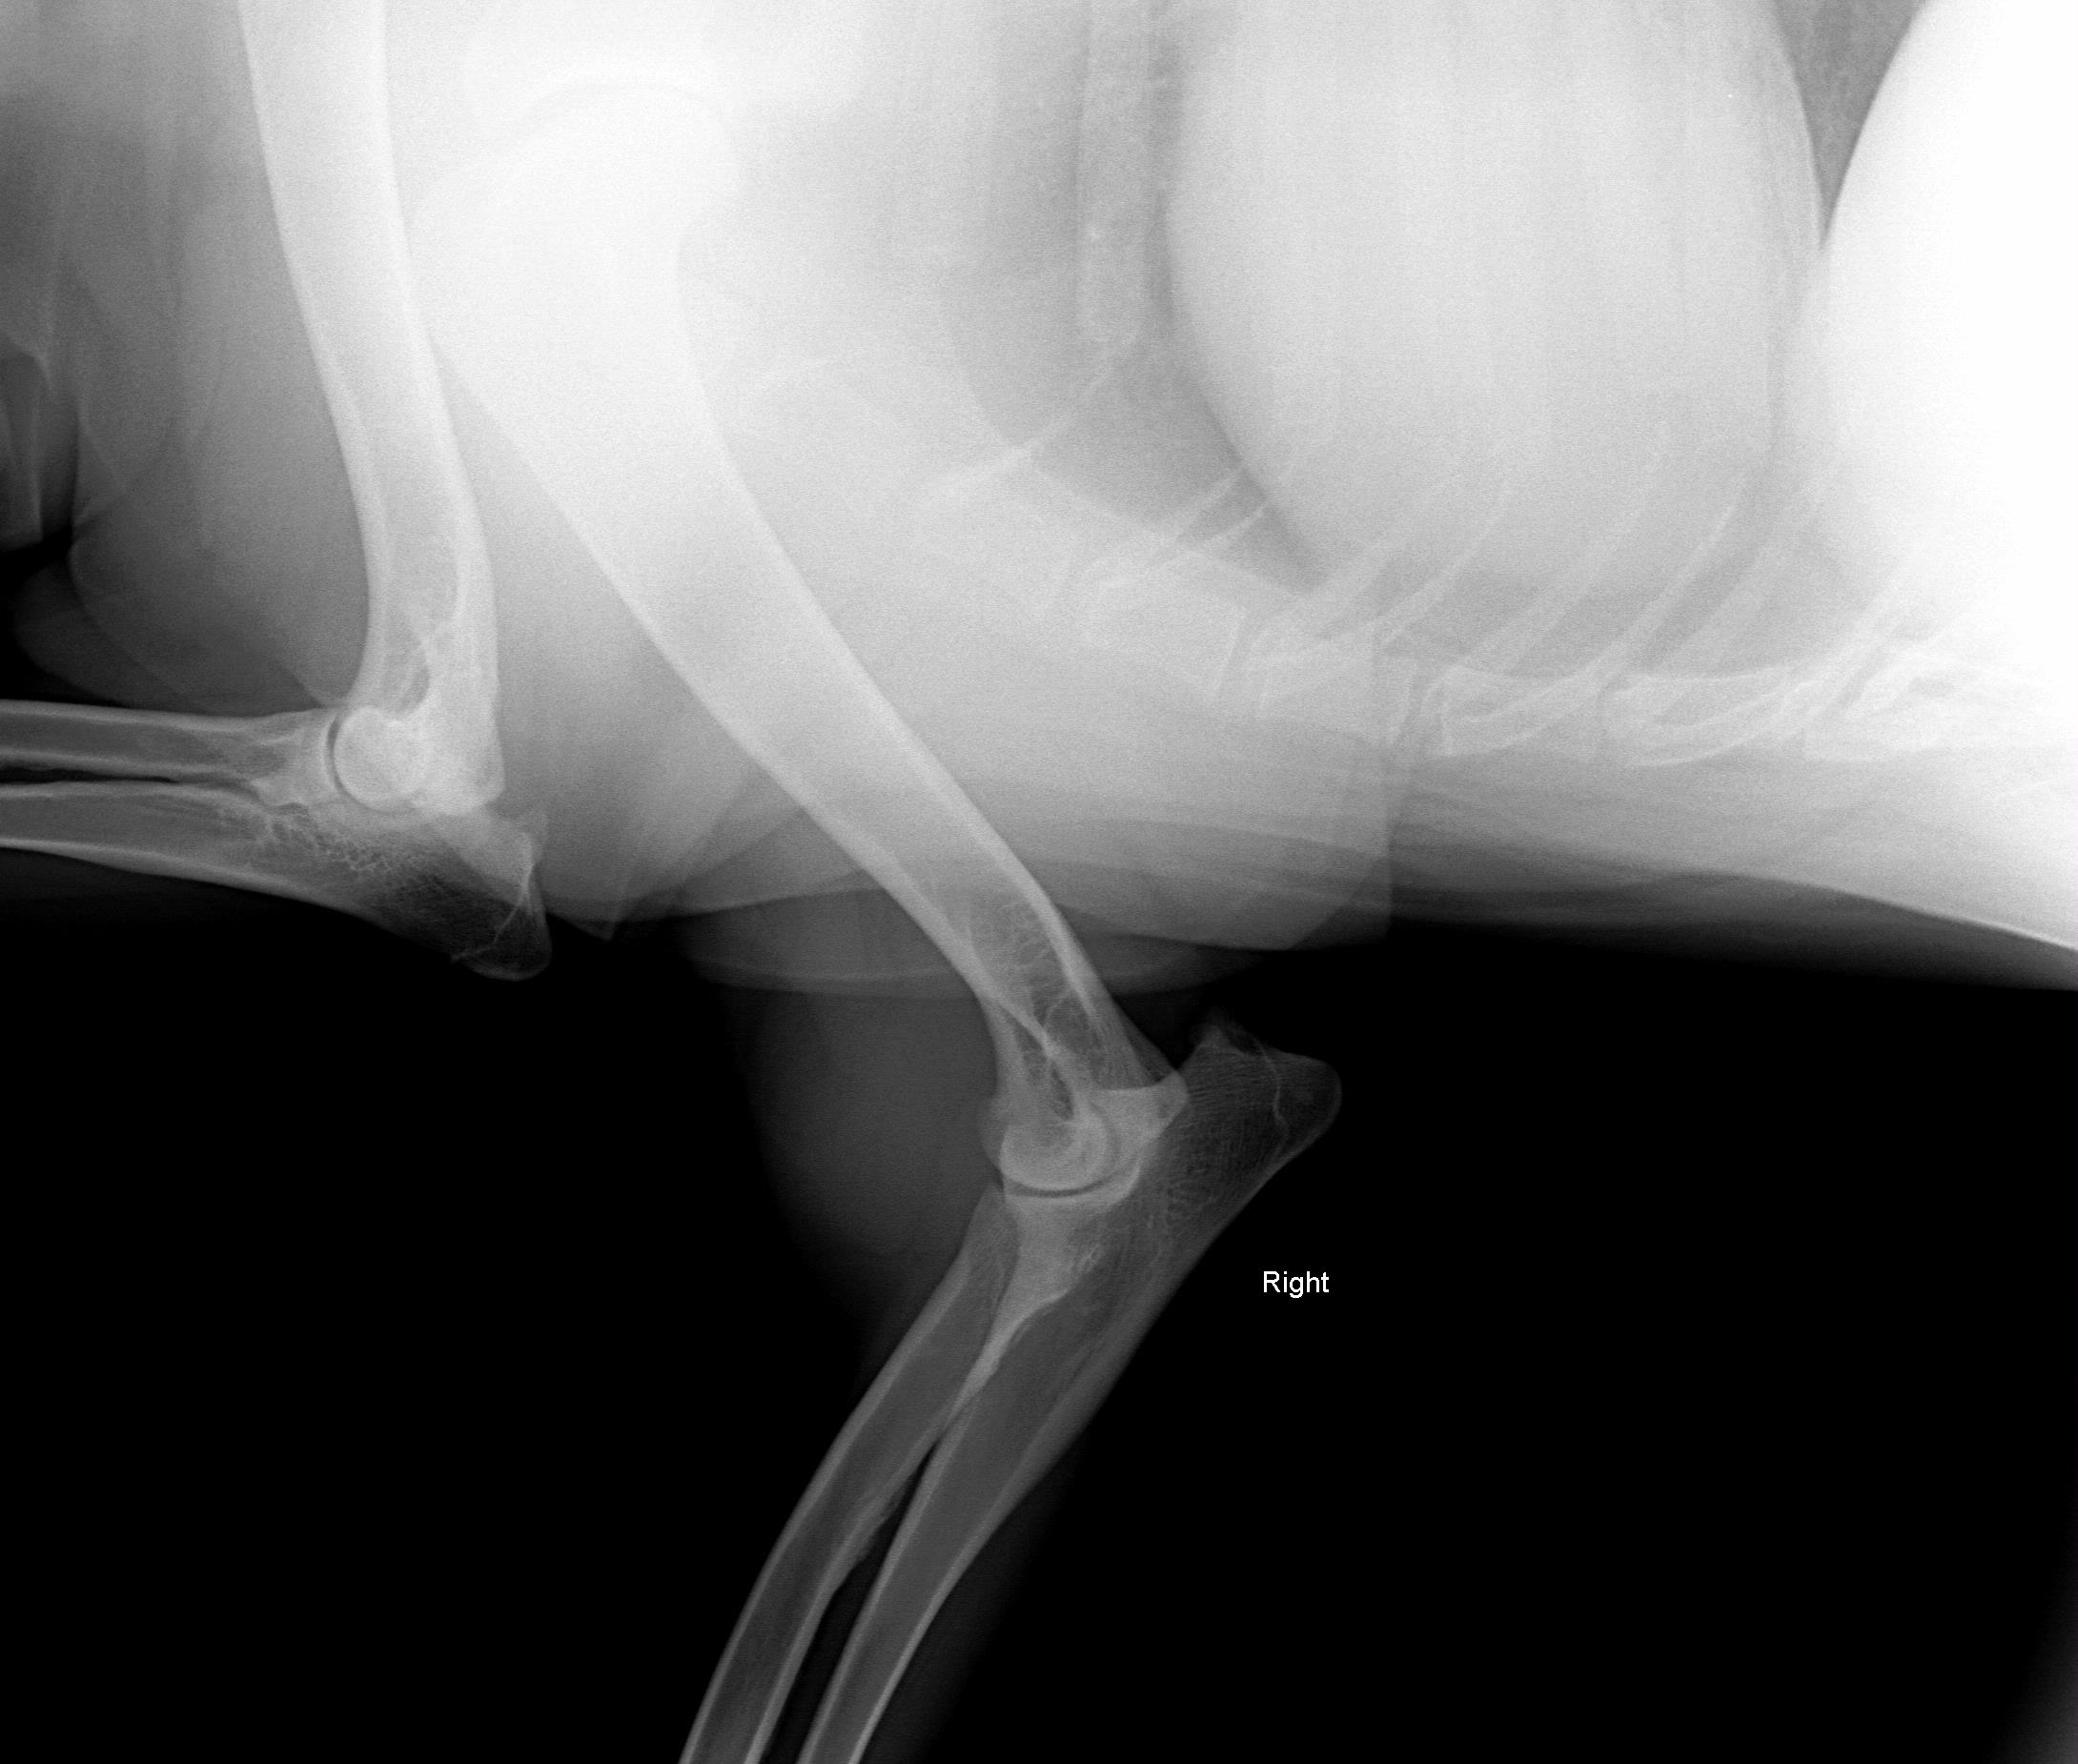

Things are not looking good. We have done three separate series of x-rays on three different days and using two different radiology labs with the most recent being 2-13-09. We have done at least two series of Fine Needle Aspirations with the results being inconclusive. This lump has moved from the outside of the elbow, to the inside and now is on top of the elbow. In January we had the lump down to the size of a walnut and limited to the top of the elbow. Now it has ballooned up to the size of a softball with only reducing slightly on any given day.

Picture taken August 17, 2008 - right leg - swelling to the outside. The swelling was to the outside.

Picture taken 1/24/09 - another lump has developed. The old lump was reduced to the size of a walnut with heat pack, physical therapy/massage (3x per day)

The following pictures are from last week 2/14/09.

On July 3, 2008, after Zoey finished her pig ear she was chasing her tail and caught the corner of the wall and never recovered from her injuries.The xray was taken 2/13/09

We consulted 5 vets, 3 series of x-rays, FNA twice and no one had ever seen anything like it before.

The following xrays were taken August 2008.